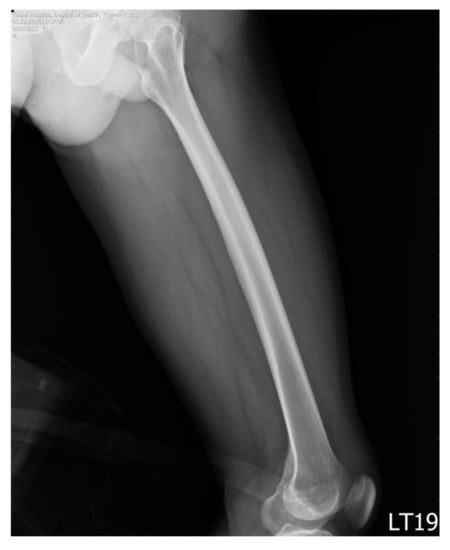

Figure 2. An example of the included images.